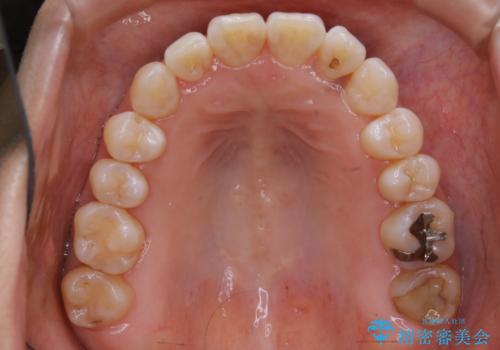

- かみ合わせ、顎のゆがみ、歯の見た目を主訴に来院された患者様です。

上の顎が下の顎に比べて小さく、それによって下の顎の位置をずらすことでしか噛めない状態でした。

また部分的に下の歯が上の歯よりも前に出てきてしまっていて、見た目にも問題がありました。

この患者様は骨格的に上あごが小さいことで問題が起きていたため、

上あごを骨ごと広げる必要がありました。

よって治療計画として、インプラントアンカーを使用した上顎急速拡大装置(MARPE)を使用することといたしました。

上あごの裏側(口蓋)に装置をマイクロインプラントで固定し、ネジを回すことで上あごを骨ごと広げていく装置です。